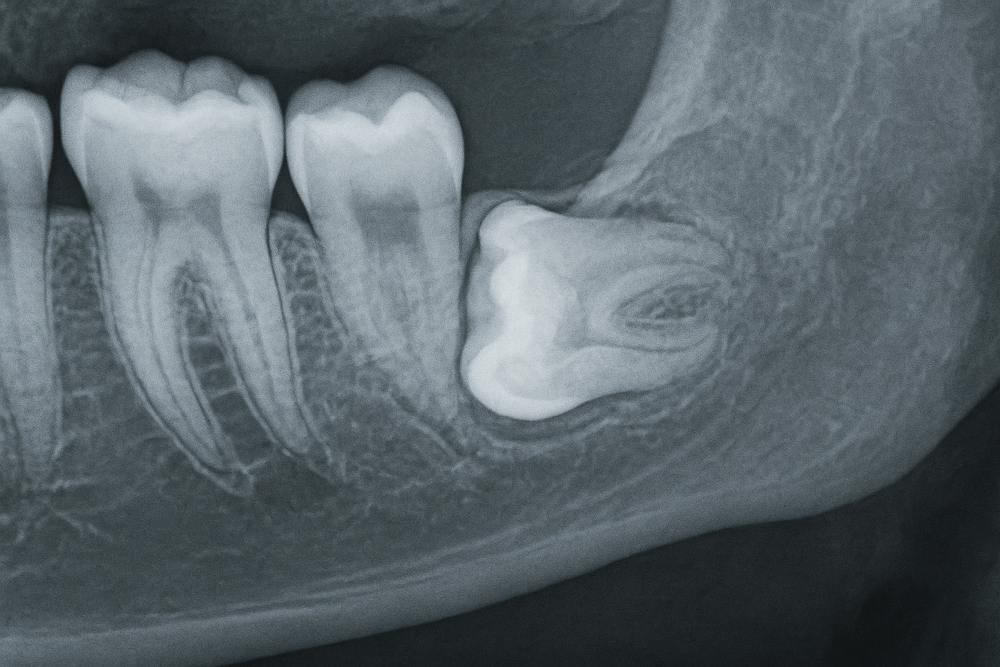

대학병원에 가야하는 사랑니 발치